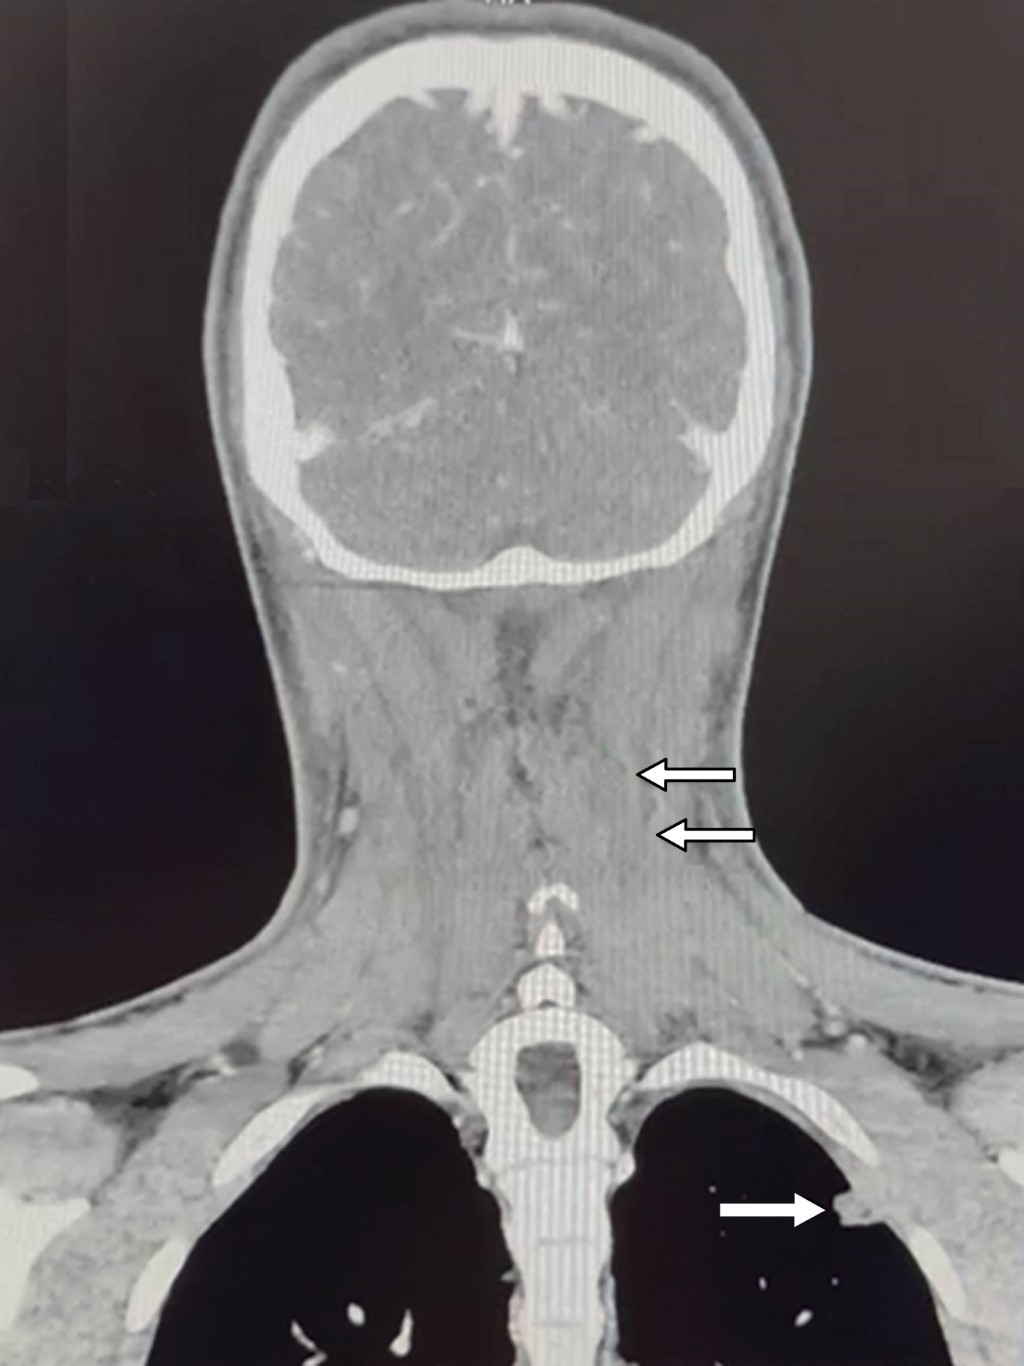

Introducción: Staphylococcus aureus es un agente causal común de infecciones de piel y tejidos blandos en la población pediátrica. Sin embargo, puede provocar enfermedades invasivas como infecciones osteoarticulares, neumonía y bacteriemia. Este caso clínico describe la progresión de una infección cutánea superficial en un adolescente que evolucionó a una afección invasiva grave. Presentación del caso: paciente de 16 años, previamente sano, quien presentó una lesión cutánea en la región cervical. En cuestión de días, la infección progresó rápidamente, provocando fiebre, malestar general y síntomas sistémicos. Los hemocultivos confirmaron la presencia de S. aureus resistente a la meticilina, y los estudios de imagen revelaron émbolos pulmonares. Se inició tratamiento con antibióticos de amplio espectro, ajustados según las pruebas de sensibilidad. Se observó mejoría clínica y el paciente fue dado de alta sin complicaciones. Conclusión: este caso destaca la posibilidad de que en pacientes pediátricos con infección cutánea por S. aureus progresen a una enfermedad invasiva potencialmente mortal. Por lo que es importante su reconocimiento y el tratamiento apropiados para prevenir complicaciones graves.

Figura 1

Figura 2